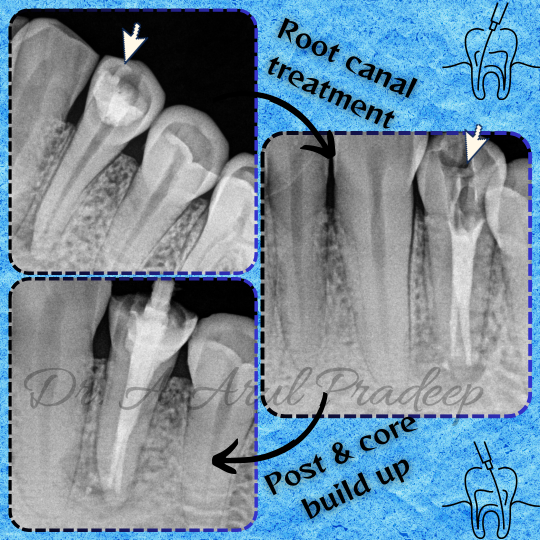

Root canal treatment in Craft32 dental care, saligramam. "🦷✨ Restoring smiles with precision! Here’s a glimpse of a successful Root Canal Treatment with Post & Core restoration. 🛠️ When decay or damage runs deep, a root canal saves the tooth, and the post & core helps rebuild its strength, giving it a solid foundation for a crown. Say goodbye to discomfort and hello to a natural, healthy smile! If you're experiencing tooth pain or sensitivity, we’re here to help. Don’t let it wait! Book your consultation today. 💙